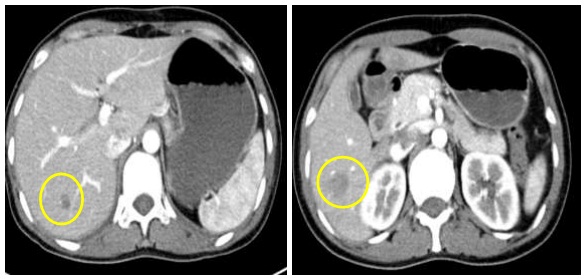

- Chụp cộng hưởng từ sọ não: Không thấy nốt ngấm thuốc bất thường.

Hình 3: Hình ảnh chụp cộng hưởng từ sọ não